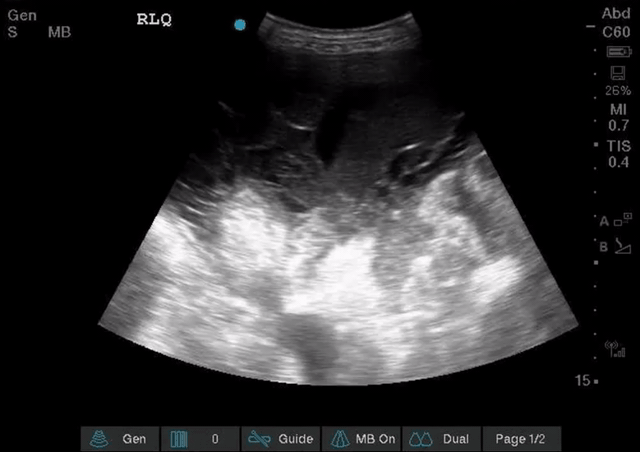

Intraluminal vs extraluminal free fluid: It is important to remember that there are numerous normal abdominal organs that are fluid filled e.g. blood vessels, stomach, gallbladder, and others that can become fluid filled in pathologic states such as small bowel or large bowel in the setting of obstruction. Especially if you are contemplating drainage you need to be certain you are draining abdominal free fluid. As a rule of thumb if fluid forms “corners” and sharp angles, settling into crevices, it is more likely EXTRAluminal and free flowing; see image on the left. If it has round borders it is most likely INTRAluminal or otherwise contained; see the image below on the right, that’s not ascites its a collection that was contiguous with bowel.